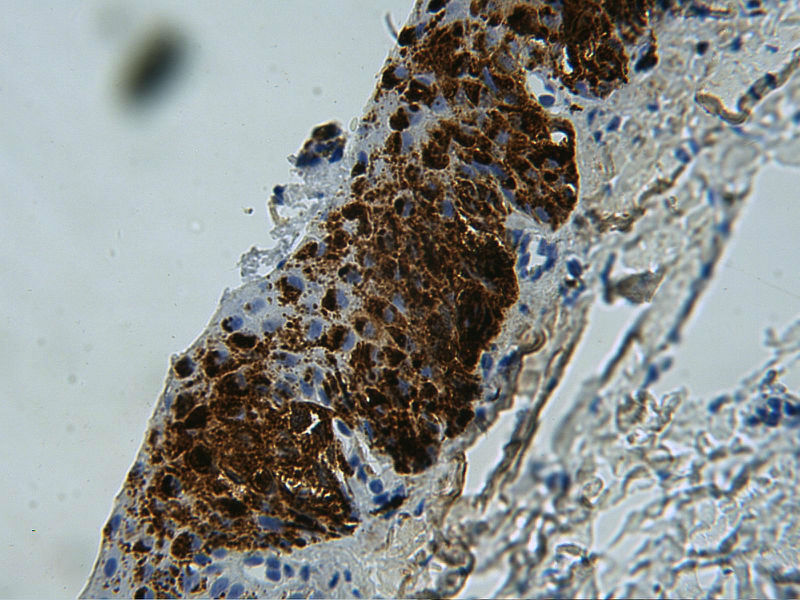

病理二:甲母痣?黑素瘤?

患者女,25岁,左无名指甲变黑1年余

HMB45

考虑原位肢端黑素瘤

考虑甲下原位黑素瘤。

需要考虑原位恶黑,无论临床和病理都支持!

临床皮损在甲根已见黑色斑,病理改变基底层黑素细胞增生活跃。要考虑原位肢端黑素瘤了。